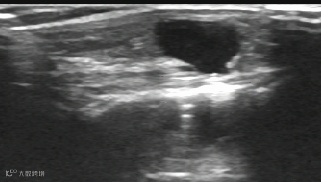

左肾囊肿硬化治疗:

治疗前

治疗后